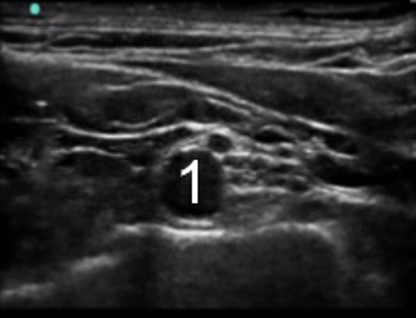

Interscalene Nerve Block 1 Image

Subclavian Artery